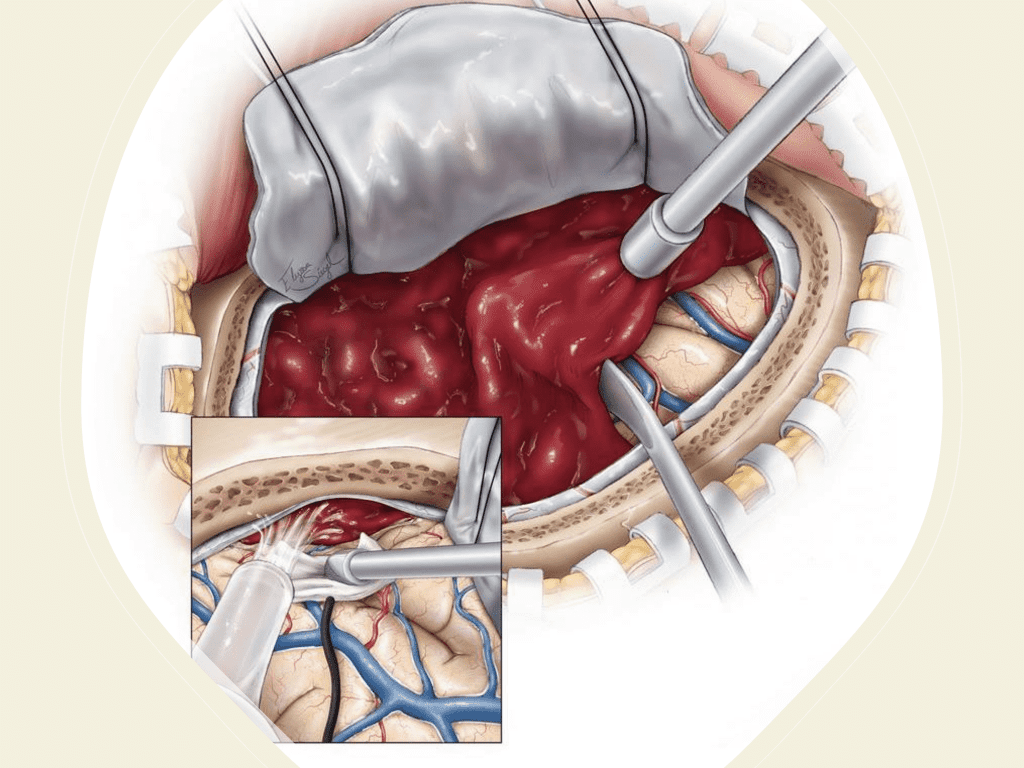

A woman in her 80s developed mild dizziness and headache following incidental trauma working in her garage one day. She presented several weeks later to the ER and was diagnosed with bilateral subdural hematomas, which were initially managed with observation, low dose Decadron, considering the mildness of symptoms, advanced age, and history of CLL with thrombocyptopenia (<100k). Over the next 4 weeks, the collections remained relatively stable with evidence of slight growth (10 to 12 mm thickness, and 2 mm right to left shift) on NCT (Figure 1. A and B).

Figure 1. A) 6 weeks post mild trauma B) 4 weeks post mild trauma demonstrates stable subacute subdural collections with mild growth and sulcal effacement.